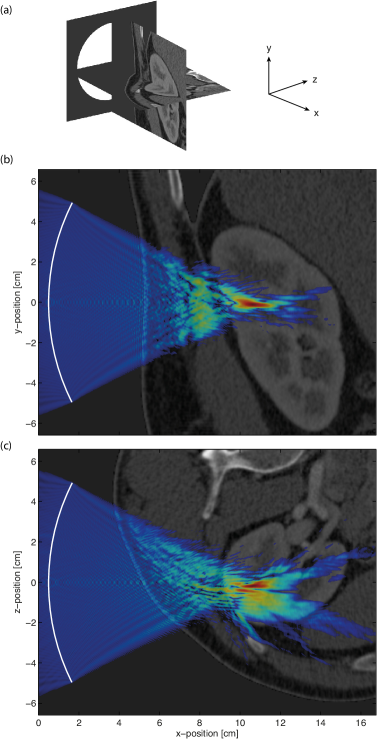

To illustrate the utility of the developed nonlinear ultrasound model for solving real-world problems, a complete large-scale nonlinear ultrasound simulation representing a single HIFU sonication of the kidney was performed. The medium properties for the simulation were derived from an abdominal CT scan (the MECANIX dataset available from http://www.osirix-viewer.com/datasets/). This was resampled using linear interpolation to give the appropriate resolution. The density of the tissue was calculated from Hounsfield units using the data from Schneider et al. [52], and the sound speed was then estimated using the empirical relationship given by Mast [57]. The remaining material properties were assigned book values [44]. The HIFU transducer was defined as a circular bowl with a width of 10 cm and a focal length of 11 cm. The shape of the transducer within the 3D Cartesian grid was defined using a 3D extension of the midpoint circle algorithm [54]. The transducer was positioned behind the patient as shown in Fig. 8(a), and was driven at 1 MHz by a continuous wave sinusoid. The acoustic intensity at the transducer surface was set to 2 W/cm2 to simulate a treatment that would likely operate largely in a thermal regime (i.e., with minimal cavitation). Outside the body, the medium was assigned the properties of water [44]. The total domain size was 17 cm ×\times 14.3 cm ×\times 14.3 cm and the grid spacing in each Cartesian direction was set to 93 μ𝜇\mum, giving a total grid size of 2048 ×\times 1536 ×\times 1536 grid points and a maximum supported frequency of 8 MHz (i.e., eight harmonics of the source frequency). The simulation length was set to 220 μs𝜇𝑠\mu s with a CFL number of 0.18, giving a total of 19800 time steps. Simulations of this scale and complexity have not previously been possible.

Refer to caption

Figure 8: (a) Sagittal and transverse slices through the abdominal CT scan used to define the material properties for simulating a HIFU treatment of the kidney. The approximate position of the HIFU transducer is shown with a white circle. (b)-(c) Saggittal and transverse slices through the simulated distribution of maximum pressure overlaid onto the corresponding CT slices. The pressure distribution is displayed using a log-scale and is thresholded at -30 dB. The distortion of the HIFU focus due to the body wall and the fat layer surrounding the kidney is clearly visible.

The simulation was executed using 768 cores on VAYU with seven checkpoint-restart stages. The total wall-clock time was 31 hours and 20 minutes, and the total memory used was 780 GB. The compressed input file was 45 GB, while the output file was 450 GB. This comprised 36 GB to store the peak positive and peak negative pressure across the domain, and 414 GB to store the time varying pressure and particle velocity for 6 periods in steady state over a 45 mm ×\times 30 mm ×\times 30 mm region surrounding the HIFU focus. Transverse and sagittal slices through the peak positive pressure overlaid onto the corresponding CT data used to define the material properties are shown in Fig. 8(b)-(c). The distortion of the ultrasound focus due to the body wall and the fat layer surrounding the kidney is clearly visible. These effects have been noted clinically, and remain a barrier to the application of HIFU in the kidney [58]. Thus, one possible future application of the developed k𝑘k-space model would be a systematic investigation into the conditions necessary for viable HIFU ablation in the kidney (for example, the maximum thickness of the fat layer). In any case, the example serves to illustrate the utility of the implementation.